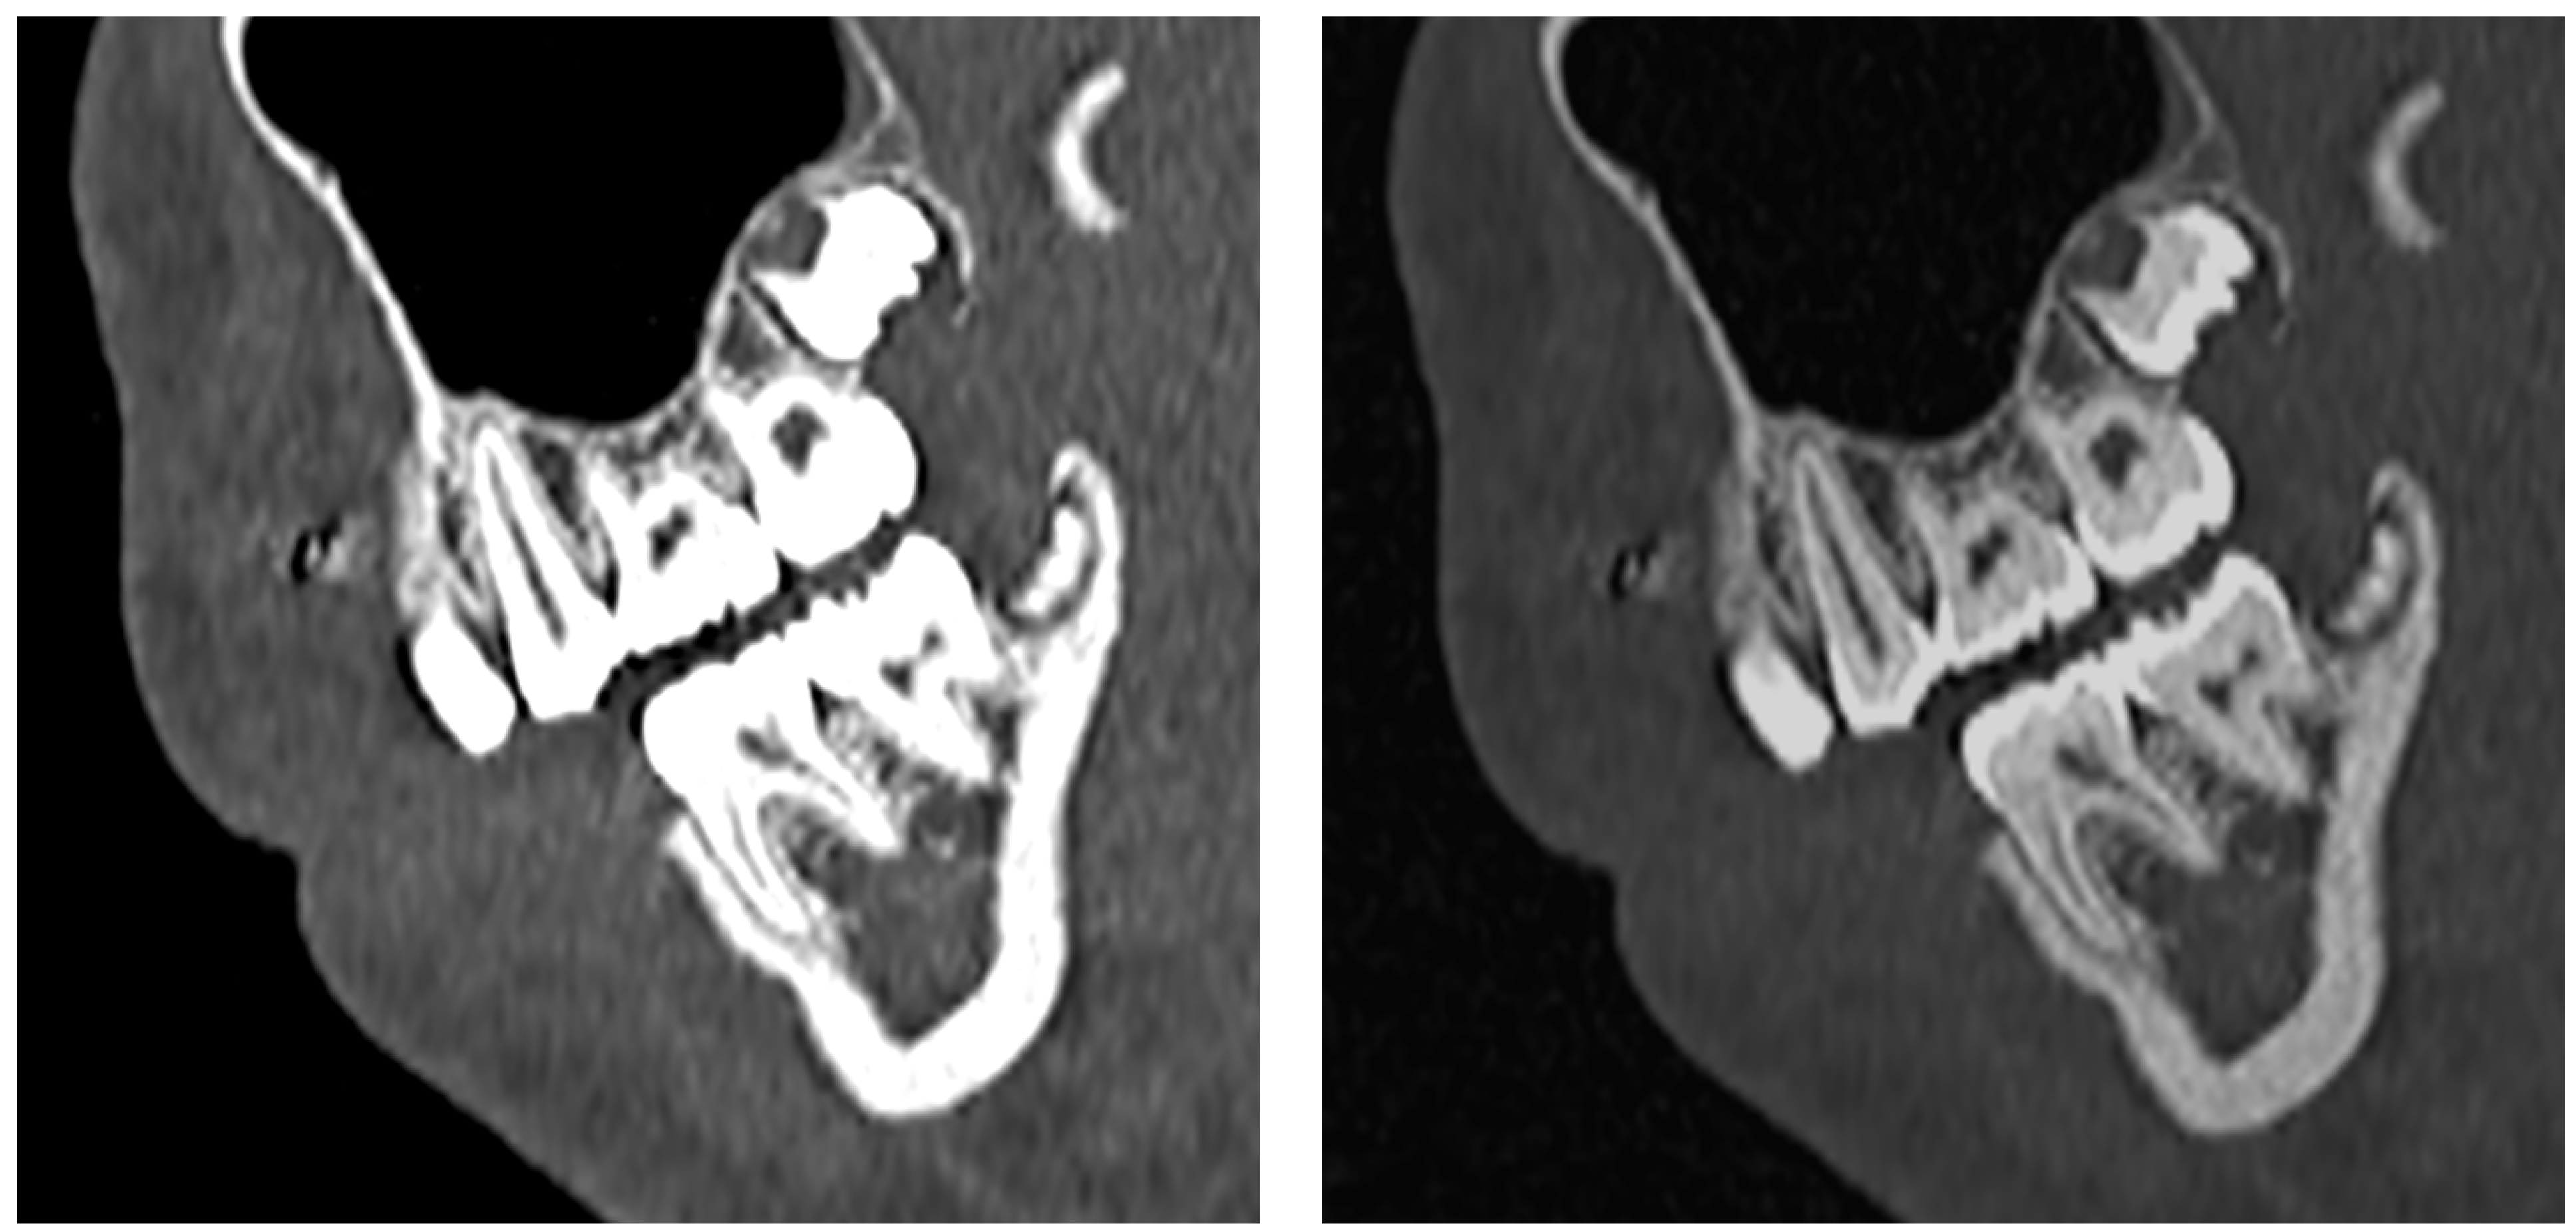

3.1. Anatomy of the Dental Arch

3.1.1. Anatomy of Tooth Structure

3.1.2. Periodontal Tissues